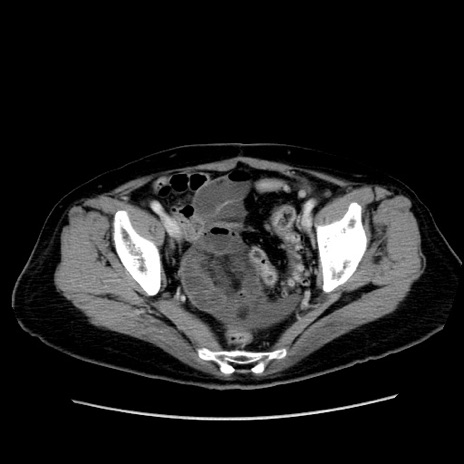

症例19(横断像)

【症例】80歳代女性

【主訴】下腹部痛

【現病歴】約8時間前より下腹部痛の出現あり、救急外来受診。

【既往歴】両側付属器切除

【身体所見】意識清明、下腹部正中に手術痕あり、その部位に一致して圧痛と反跳痛あり。腸蠕動音は亢進。

【データ】WBC 9300、CRP 0.15